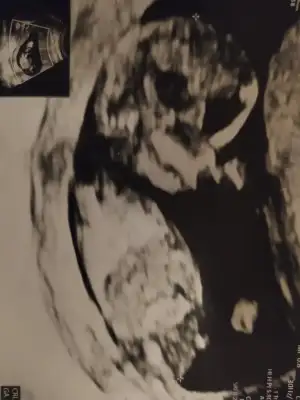

Ikra meyra Ikra meyra canım benim ve ablamın bebişlerinin cinsiyetini sen bildin🥰 buda yakın dostumun ultrason görüntüsü 10+6 da . Tahminlerini bekliyorum🥰🙏🏻

Merhaba , tahmin yürütebilir misiniz